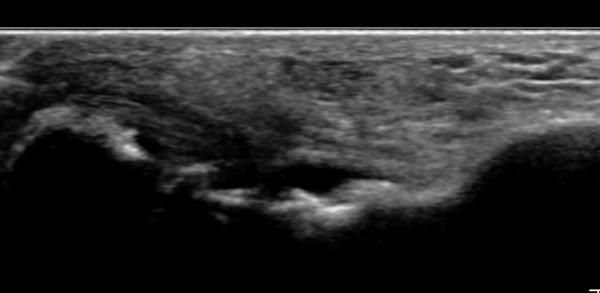

ÃÊÀ½ÆÄ°Ë»ç : ¹ß¸ñ °üÀý Á¾´Ü¸é°Ë»ç¿¡¼­ ¹ß¸ñ °Å°ñ ¿¬°ñÀÌ ¾ã¾îÁ®(thinning) º¸ÀδÙ(»çÁø 1).